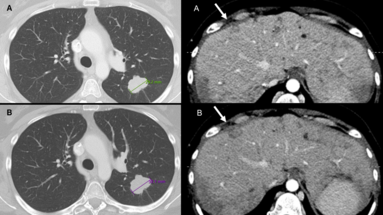

Advancing Neuro-Oncology Assessments: Mint Medical to Integrate Newly Published RANO 2.0 Criteria into mint Lesion™

Glioblastomas and other gliomas are the most common malignant primary brain tumor types, yet few effective therapies are available. Clinical research and clinical trials are essential in supporting…